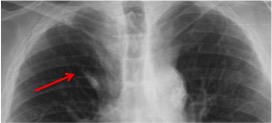

CASO: Disnea. Paciente con insuficiencia cardiaca.

Hallazgos:

- Cardiomegalia.

- Signo del 3º mogul y doble contorno por crecimiento de la aurícula izquierda.

- Bronquio izquierdo rectificado por crecimiento de la aurícula izquierda (signo de la bailarina).

- En la placa lateral, además se observa elongación aórtica.

- Parénquimas pulmonares sin hallazgos.

Signo del doble contorno: La AI aumentada de tamaño produce un segundo contorno que normalmente no debería figurar (flecha naranja contínua).

Flecha amarilla: cayado aórtico.

Flecha verde: arteria pulmonar.

Flecha azul: ventrículo izquierdo.

Signo del tercer mogul: se refiere a la lobulación anormal del contorno mediastínico izquierdo entre la arteria pulmonar y el ventrículo izquierdo. Pueden producir esta lobulación lesiones cardíacas y pericárdicas (orejuela izquierda aumentada, aneurisma ventricular o de la arteria coronaria, quiste o masa pericárdicos, etc) y también algunos tumores mediastínicos, como timomas. En la imagen, el signo corresponde al crecimiento de la orejuela izquierda (flecha roja). La palabra “mogul” es un término utilizado por los esquiadores para describir un acúmulo mamilar de nieve compacta en una ladera montañosa. El primer mogul corresponde al cayado aórtico (flecha amarilla); el segundo, a la prominencia de la arteria pulmonar (flecha verde); y el cuarto, al contorno del ventrículo izquierdo (flecha azul).

Signo del doble contorno: indicativo de crecimiento de la aurícula izquierda en la radiografía posteroanterior de tórax. La aurícula izquierda no forma parte normalmente del contorno cardiaco derecho en esta proyección; sin embargo, cuando aumenta de tamaño, produce un segundo contorno (flecha narana contínua), además del de la aurícula derecha (flecha naranja discontinua).

Signo de la bailarina: es un signo de crecimiento de la aurícula izquierda visible en la radiografía posteroanterior o anteroposterior de tórax, y consiste en el aumento del ángulo traqueal por levantamiento del bronquio principal izquierdo (flecha rosa). El nombre del signo se debe al parecido de la imagen con la apertura de piernas (spagat) de una bailarina.